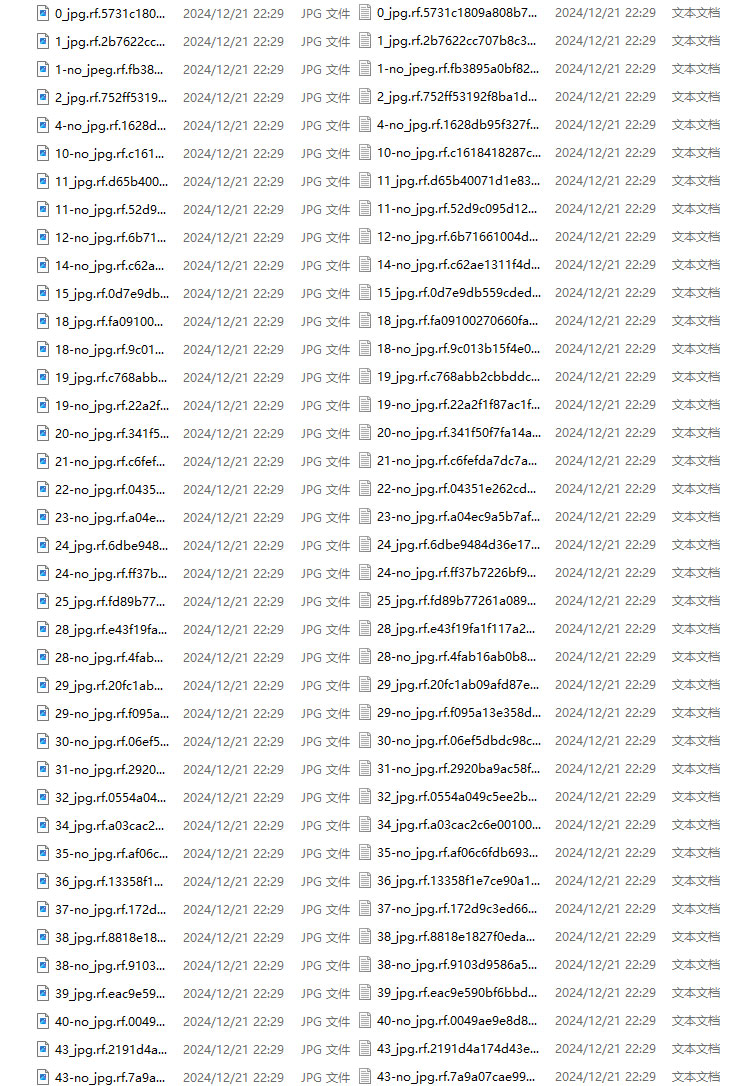

(3)数据准备

这里建议新建一个名为data的文件夹(这个是约定俗成,不这么做也行),里面创建一个名为images的文件夹存放我们需要打标签的图片文件;再创建一个名为labels存放标注的标签文件;最后创建一个名为 classes.txt 的txt文件来存放所要标注的类别名称。

data的目录结构如下:

│─img_data

│─images 存放需要打标签的图片文件

│─labels 存放标注的标签文件

└ classes.txt 定义自己要标注的所有类别(这个文件可有可无,但是在我们定义类别比较多的时候,最好有这个创建一个这样的txt文件来存放类别)

首先在images这个文件夹放置待标注的图片。

生成文件如下: